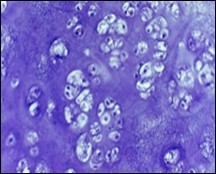

Characteristically, enchondroma is below < 5 centimetre magnitude although enlarged lesions can be considered benign when accompanying indeterminate or atypical microscopic features are absent4, 5. Enchondroma is composed of well-circumscribed nodules of benign hyaline cartilage. Incorporated chondrocytes demonstrate miniature, uniform, spherical nuclei with condensed chromatin. Bi-nucleate cells are infrequent4, 5.

Typically, chondroid matrix of an enchondroma depicts foci of punctate calcification. Tumour cell nuclei are fairly uniform. Mitotic figures are few. Extensively calcified enchondromas are associated with foci of endochondral ossification 4, 5.

The neoplasm is configured of lobules of hyaline cartilage enveloped by perichondrium-encased bone. Tumefaction can be hyper-cellular with bi-nucleate tumour cells. Myxoid change, foci of calcification and endochondral ossification are discerned. Necrosis may ensue on account of avascular cartilaginous component. Tongues of bone appear to extend into subjacent cartilage demonstrating a sharply defined interface confined to the growth plate4, 5.

Benign, juxta-cortical enchondroma arising within miniature, tubular bones as the hand may be hyper-cellular and demonstrate cellular and nuclear atypia 5.

Distinction between benign cartilaginous lesions and atypical cartilaginous tumour or grade 1chondrosarcoma (ACT/CS1) can be challenging, Typically, benign cartilaginous lesions are hypo-cellular, in contrast to hyper-cellular atypical cartilaginous tumour or grade 1 chondrosarcoma 5, 6. Figure 1, Figure 2, Figure 3, Figure 4, Figure 5, Figure 6, Figure 7, Figure 8.

Figure 4.Enchondroma depicting lobules of hyaline cartilage with vacuolated cells and eccentric nuclei 12.

Figure 5.Enchondroma enunciating lobules of uniform cartilaginous cells with regular, centric nuclei and absence of mitosis 13.

Figure 6.Enchondroma exemplifying lobules of hyaline cartilage composed of enlarged, vacuolated cells with uniform nuclei. Focal calcification is absent 14

Figure 7.Enchondroma enunciating lobular hyaline cartilage with constituent vacuolated chondrocytes an uniform nuclei 15.

Figure 8.Enchondroma delineating hyaline cartilaginous cells with vacuolated cytoplasm and uniform nuclei 16.